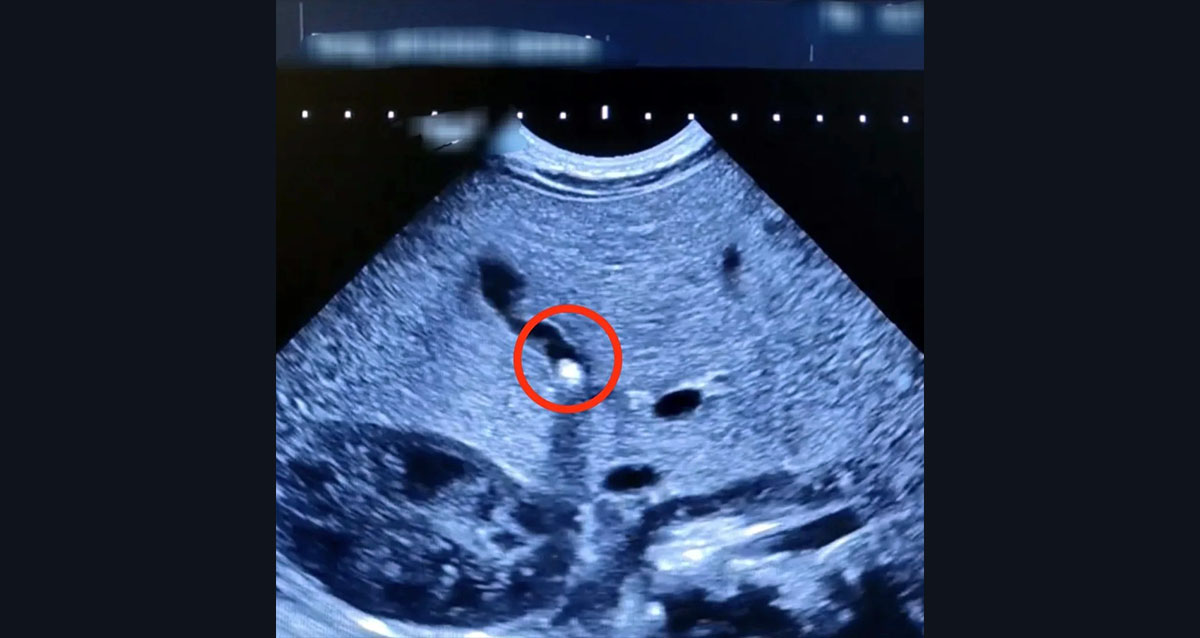

Маленький пациент поступил в стационар с желтухой и плохой прибавкой в весе. При проведении УЗИ специалисты обнаружили, что желчный проток частично перекрыт небольшим конкрементом. Это заболевание, характерное для взрослых и пожилых людей, стремительно «молодеет», но выявление у ребенка в возрасте 1,5 месяца – исключительная редкость.